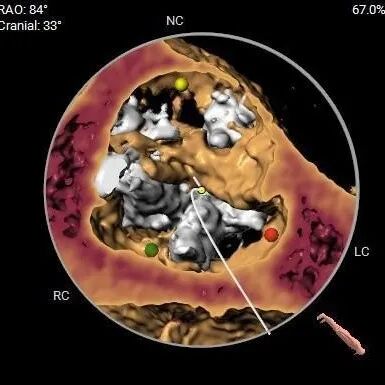

Type1型二叶式主动脉瓣,L-R钙化融合,LVOT近似直筒,近似横位心

重度钙化,HU 850积分999mm3

左冠12.2,右冠16.6,综合分析冠脉阻挡风险适中

瓣上多平面分析